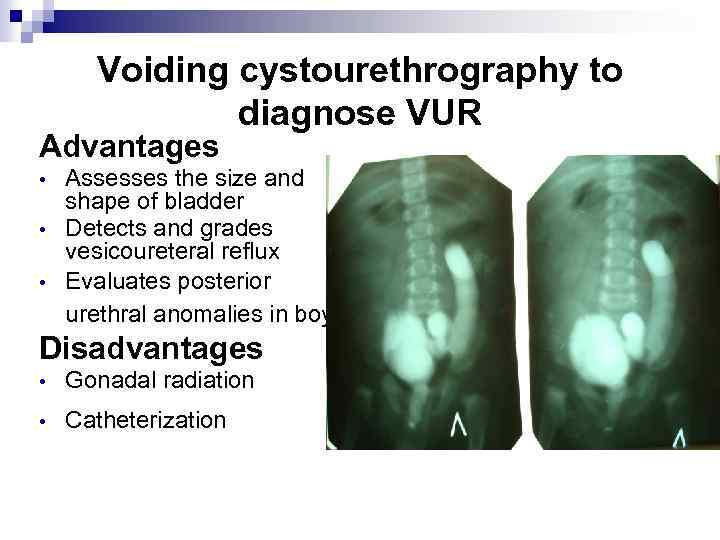

Voiding cystourethrography to diagnose VUR Advantages • • • Assesses the size and shape of bladder Detects and grades vesicoureteral reflux Evaluates posterior urethral anomalies in boys Disadvantages • Gonadal radiation • Catheterization

Voiding cystourethrography to diagnose VUR Advantages • • • Assesses the size and shape of bladder Detects and grades vesicoureteral reflux Evaluates posterior urethral anomalies in boys Disadvantages • Gonadal radiation • Catheterization